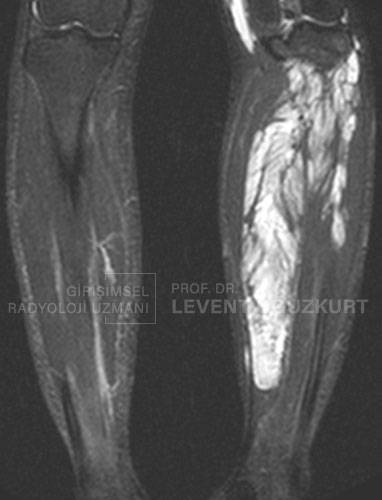

Uyluk emar inceleme

Uyluk bölgesind ebeyaz renkle görünen kısım damar anormalliğini gösteriyor.